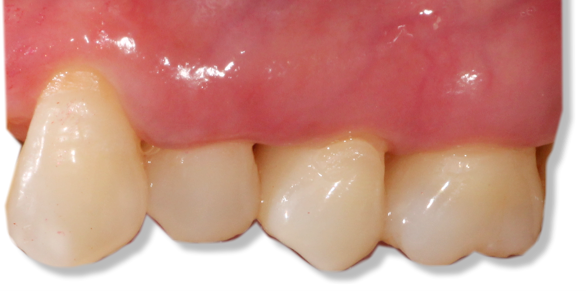

![]() | ![]() |

| Before and after surgery to reshape gums | X-ray showing results before and after bone graft surgery |